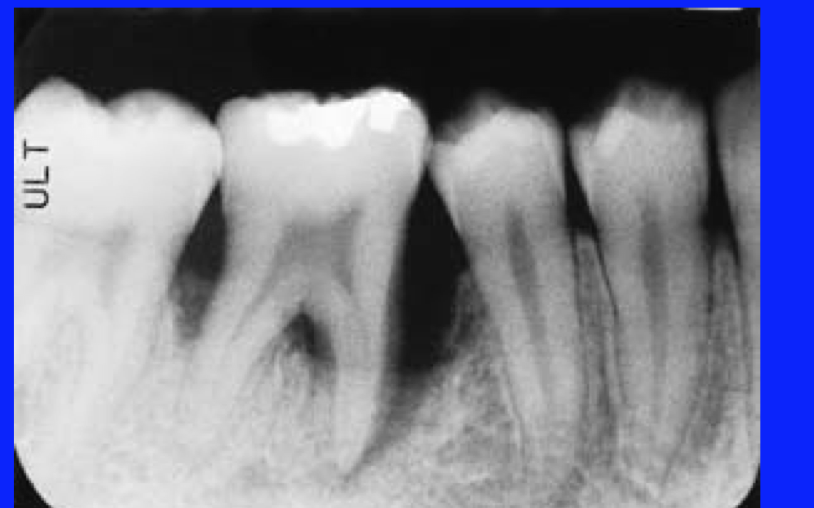

localized juvenille perio

localized juvenile perio